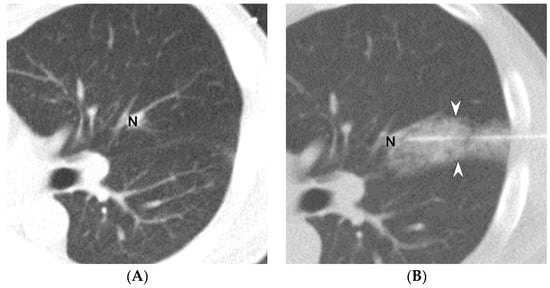

2.2. Methods for CT-Guided Localization with PBV Dye